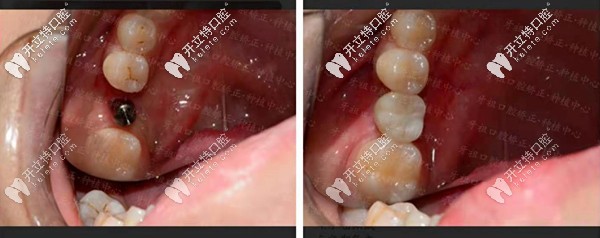

【種植牙案例一】單顆種植牙修復(fù),還原咬合力!

長(zhǎng)沙牙祖口腔周磊種植案例一

顧客情況:女性,19歲,右下6號(hào)牙殘根不能保留。

種植方案:拔除殘根牙后做種植處理。

種植周期:3個(gè)月